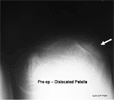

Physical examination: 45 degree genu valgus with the Q angle at 15 degrees Patellar was dislocated and not reducible True length discrepancy of 5 centimeters

Radiographs: Arrest of the lateral femoral physis The tibio-femoral angle was measured to be 34 degrees Patella dislocated laterally